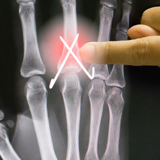

Choosing the right hand Therapist starts with them being able to read your X-rays and then fabricate the right brace for you. The therapists at Action Rehab are experienced in assessing and reading X-rays.

Our therapists do regular GP and Emergency Doctor training and can advise on the most appropriate action for your Fractured Finger treatment.